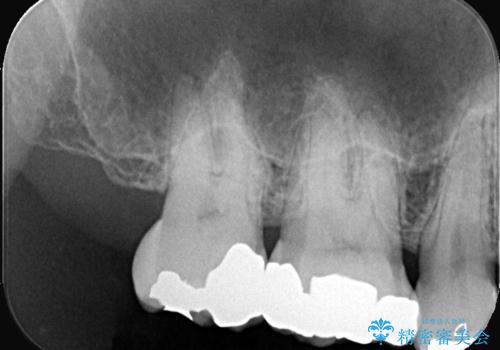

今回も不適合な銀歯を外したらその下は虫歯になっていました。

虫歯を除去後、フルジルコニアクラウンで治療を行いました。

不適合な銀歯を外して、虫歯の除去後にシリコンで印象をとりフルジルコニアクラウンで治療を行いました。